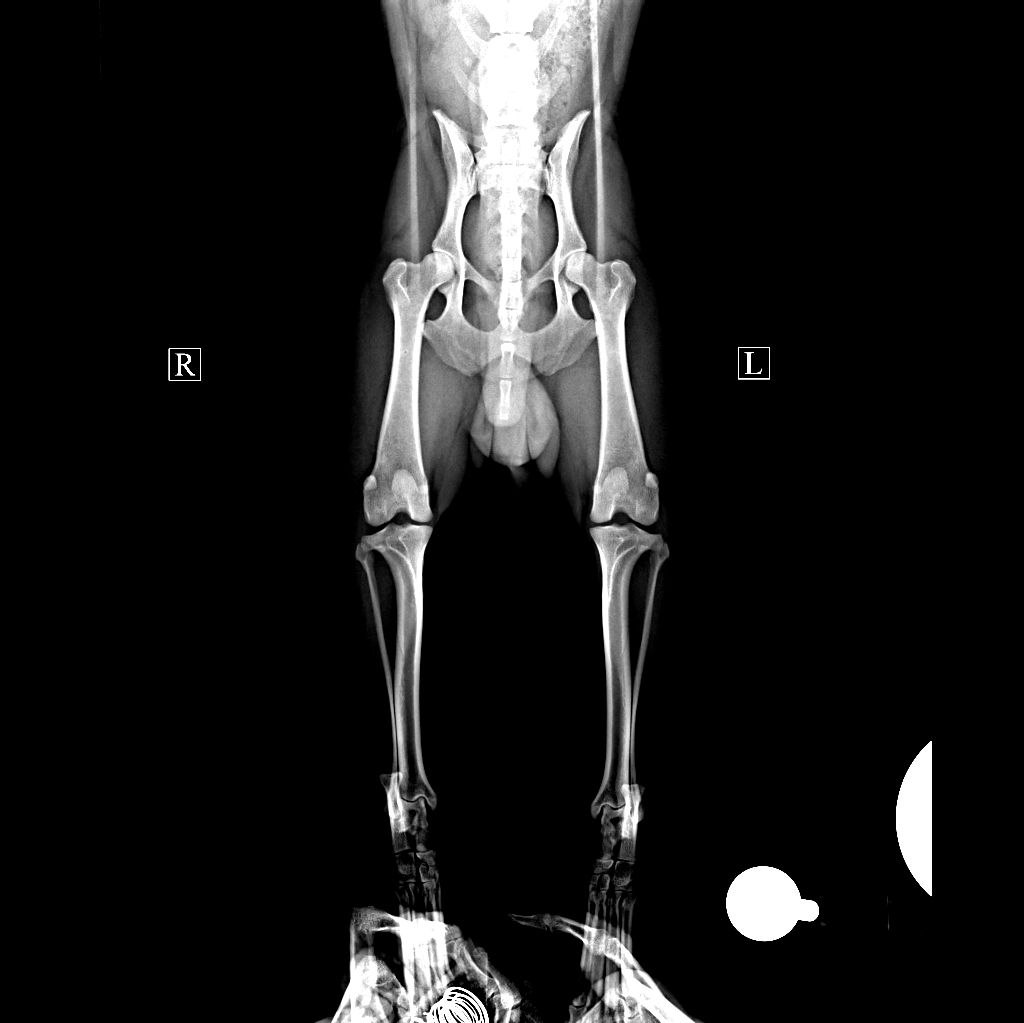

Завтра УЗИ и на четверг записались к Дудкину по лапе.

Мы не согласны и рентген надо сделать.

УЗИ, сделали обширное, разница в цене не существенна.

Заодно посмотрели поджелудочную, Огородникова никогда её не визуализирует.

Все подробно в процессе объясняла, хотя я и УЗИ далеко, но микролиты в мочевом и почках видно однозначно.